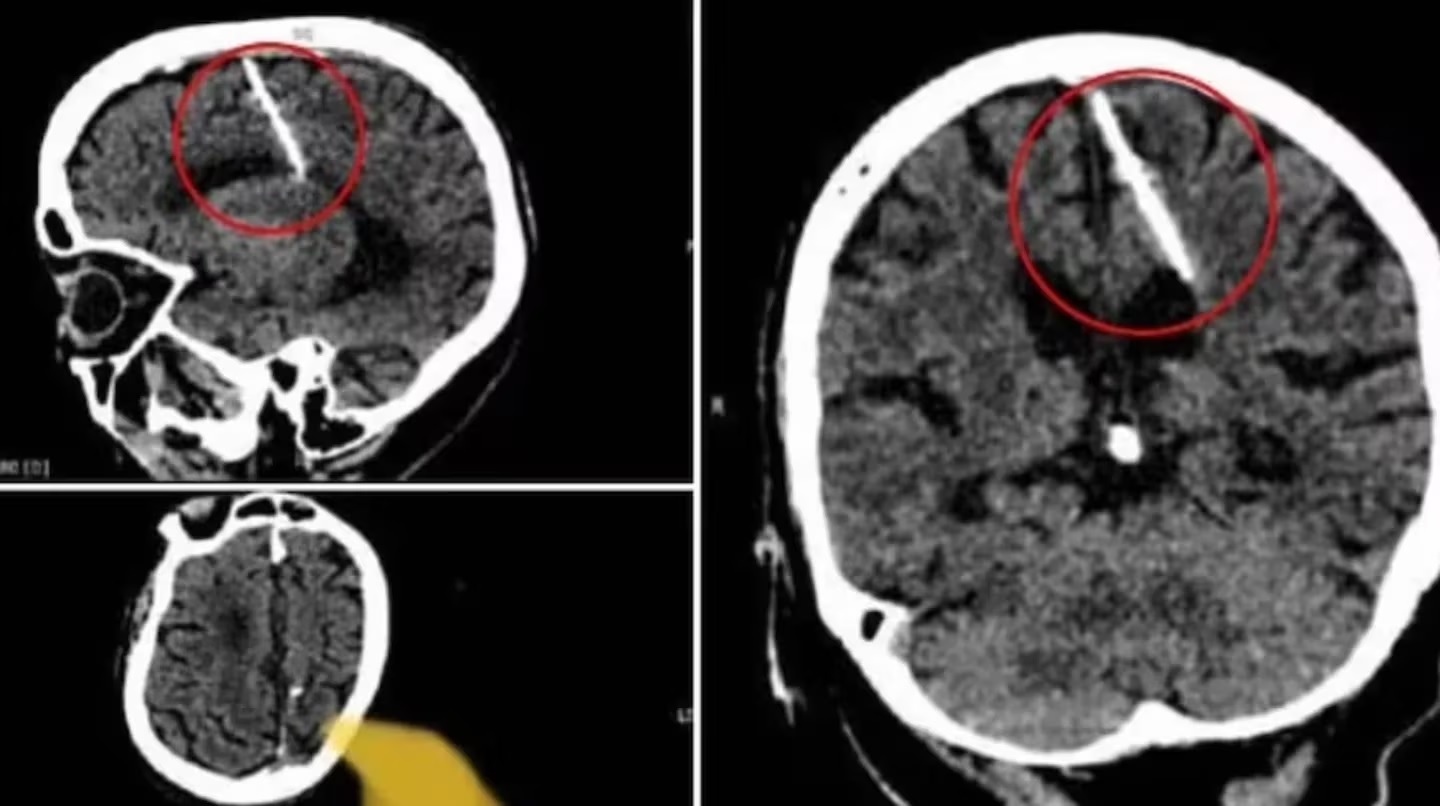

En Sajalín, una isla de Rusia, una mujer de 80 años fue a hacerse una tomografía a un centro médico y descubrió algo que la descolocó: los resultados demostraron que tenía una aguja de tres centímetros insertada en el cerebro y que llevaba allí la mayor parte de su vida.

El elemento punzante se ubicaba en un sector de su lóbulo parietal izquierdo y, afortunadamente, no parecía traerle ningún tipo de secuela. Sin embargo, todo cambió cuando se enteraron la verdadera y escalofriante razón por la cual la mujer había sufrido tal lesión.

Después de obtener las inesperadas imágenes, los especialistas decidieron que lo mejor era no retirarle la aguja ya que cualquier operación cerebral podría presentar un riesgo en una persona de una edad avanzada como ella. Si bien ya era sorprendente que el elemento no estuviera causando ningún trauma, la explicación del hecho terminó por dejarlos sin palabras.

Los expertos aseguraron que ella se encuentra fuera de peligro, aunque la mantienen bajo observación debido a la delicada lesión. Según informaron, el elemento punzante está ubicado en el sector del cerebro donde se procesa la información sensorial. Aún no se explican cómo logró sobrevivir y lo califican como un “milagro”.